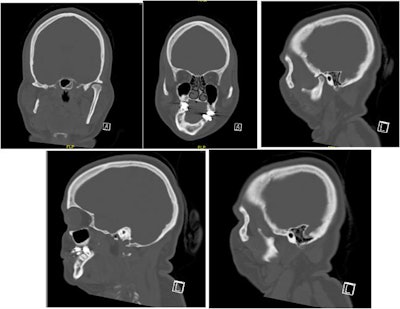

In the current case, the woman at age 2 experienced trauma to the right side of her face. By age 11, she had progressively worsened dental occlusion and facial asymmetry that affected her ability to chew. At that time, the woman was diagnosed with severe maxillomandibular deformity with functional deficits, as well as pain secondary to her right jaw failing to grow, according to the authors.

In July 2017, the woman visited the oral and maxillofacial surgery clinic due to her poor bite and facial asymmetry. A physical exam revealed that she had a severe 10-mm occlusal cant, only contacting on her right premolars and molars, with a left-sided open bite. This caused a 2-mm incisal display in repose and a negative 2-mm gum display when she smiled. When smiling, the cant caused a 3-mm gingival display on her left and a negative 4-mm gingival display on the right. Also, her chin deviated dramatically to the right of the midline of her face, the authors wrote.

The severity of the woman's skeletal malocclusion greatly increased the complexity of her reconstruction, and several treatment options were considered, the group noted. Many surgeons likely would have chosen to reconstruct her right temporomandibular joint with an alloplastic joint replacement or costochondral graft reconstruction.

In this case, they chose to perform an inverted L osteotomy without joint reconstruction because the patient's existing fibro-articulation had a good pain-free range of motion, and she had no temporomandibular joint-associated symptoms.

"Even in the setting of a missing condyle, condylar reconstruction is not always necessary, especially without condylar symptoms and with good condylar function," Vajda and colleagues wrote.